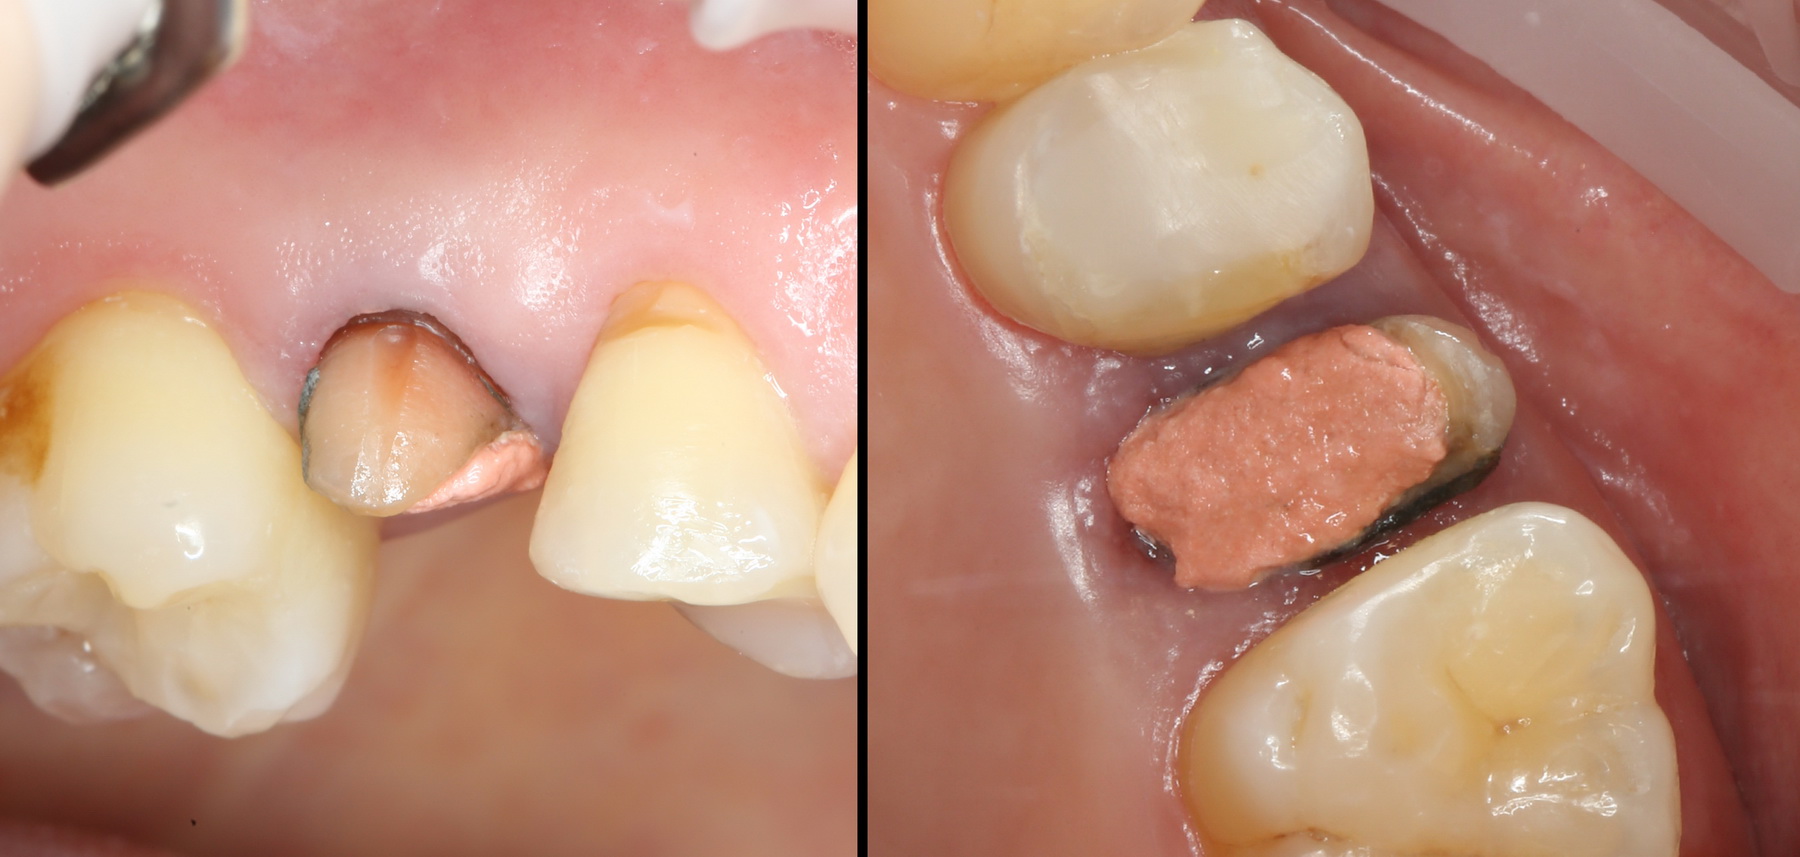

Вот исходная клиническая картинка:

К сожалению, попытка вылечить зуб эндодонтически и восстановить с помощью вкладки/коронки потерпела неудачу. Поэтому приходится его удалять.

Первое, с чего начинается удаление зуба — это разрез. С помощью скальпеля и периотома отделяется круговая связка зуба. Конкретно в этом случае важно еще увидеть границы лунки, чтобы понять пределы аугментации: